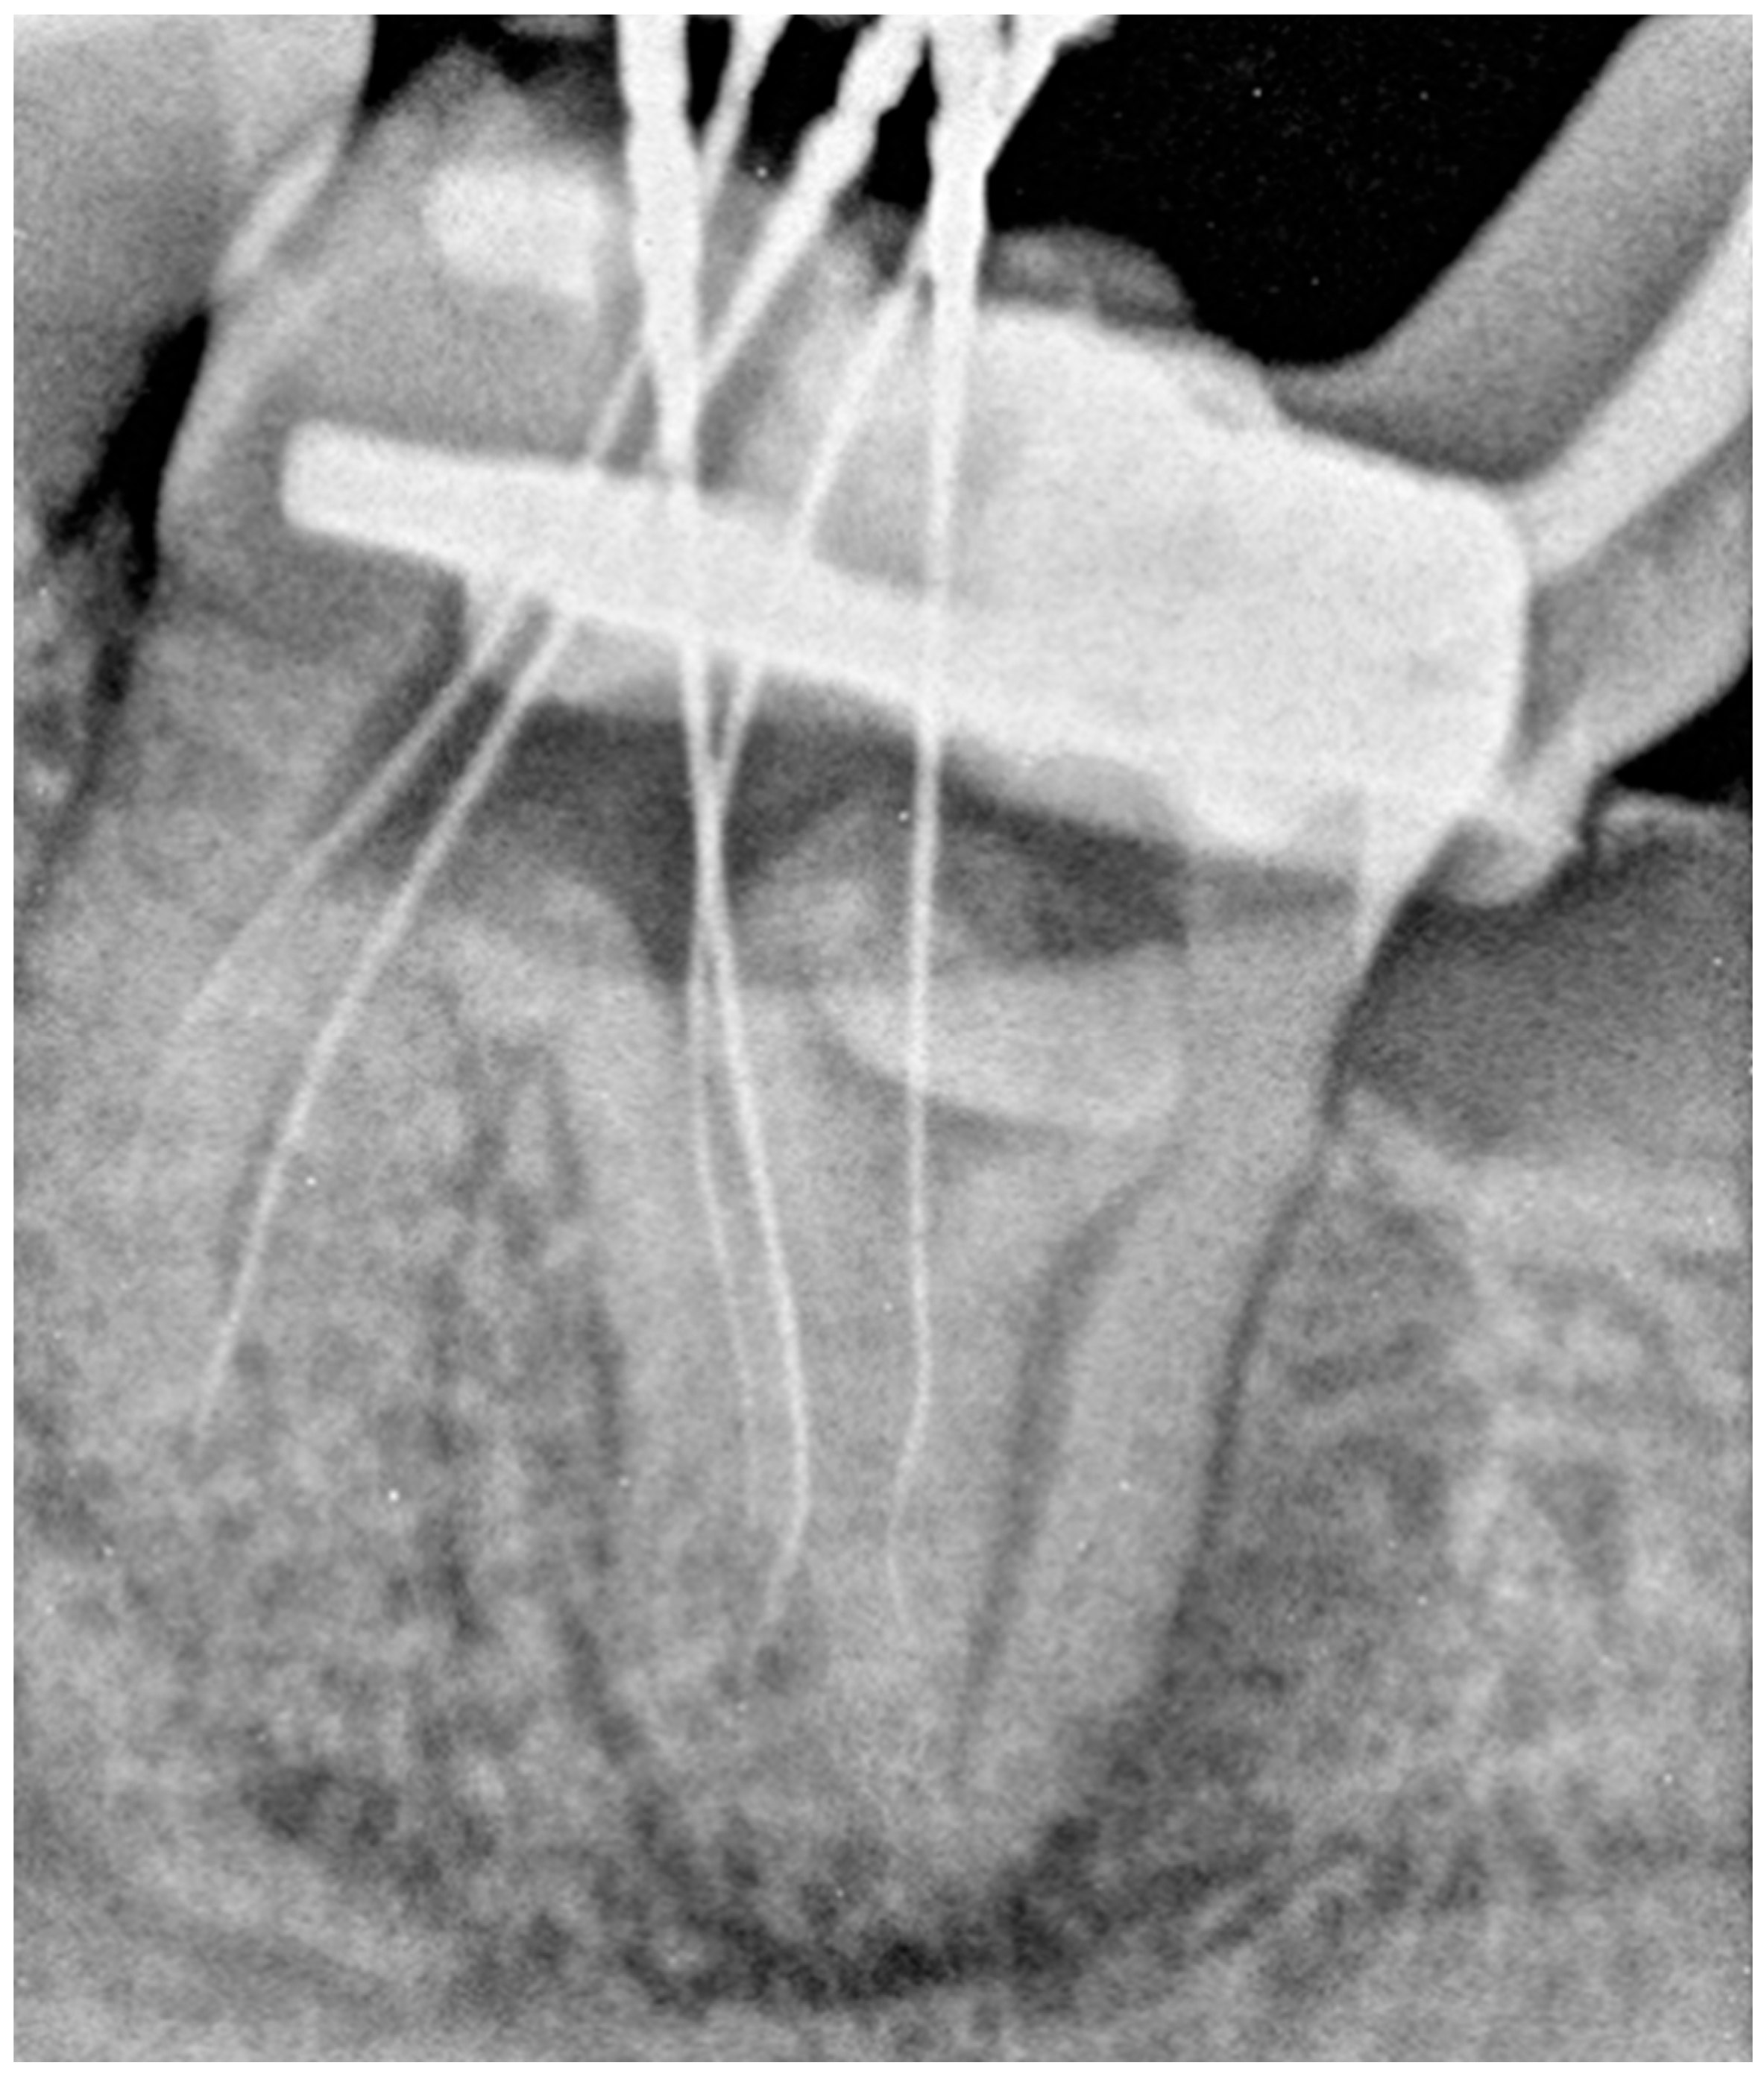

2.2. The Second Appointment

2.3. The Third Appointment

2.4. The Fourth Appointment

2.5. The Fifth Appointment

2.6. Sixth Appointment